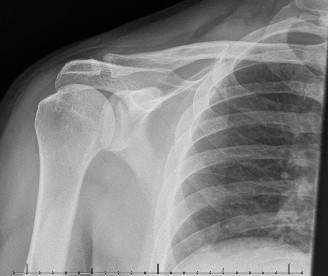

Electrodiagnostic studies (electromyography and nerve conduction velocity studies) are paramount for objective confirmation of SSNE, providing information on nerve demyelination, axonal degeneration, and the level of entrapment. Findings such as increased distal motor latency, decreased nerve conduction velocity across the notch, and denervation potentials (fibrillations, positive sharp waves) or chronic neurogenic changes (polyphasic motor units) in the supraspinatus and/or infraspinatus muscles are highly suggestive. Magnetic resonance imaging (MRI) and magnetic resonance neurography (MRN) are crucial for visualizing the nerve, identifying space-occupying lesions (e.g., ganglion cysts, labral tears), evaluating muscle edema (acute denervation) or fatty atrophy (chronic denervation), and assessing the integrity of the ligaments. Diagnostic injection of local anesthetic into the suprascapular notch can also provide temporary relief and aid in diagnosis.

- Advanced Imaging (MRI/MRN): Detailed review of imaging to identify any space-occupying lesions (ganglion cysts, labral tears, tumors), hypertrophic ligaments, or bony spurs. MRN is particularly useful for visualizing the nerve's course and potential points of compression. The relationship of a cyst to the glenohumeral joint capsule and labrum must be fully understood if a cyst is present.

- Magnetic Resonance Imaging (MRI) / Magnetic Resonance Neurography (MRN): Critical for identifying the anatomical cause of compression. Studies by Donovan et al. and Fritz et al. underscore the utility of MRN in visualizing the nerve path, identifying space-occupying lesions (ganglion cysts, paralabral cysts), and assessing muscle changes (edema in acute denervation, fatty atrophy in chronic denervation). Posterior labral tears are frequently implicated as the origin of spinoglenoid cysts (Snyder et al., Fealy et al.).